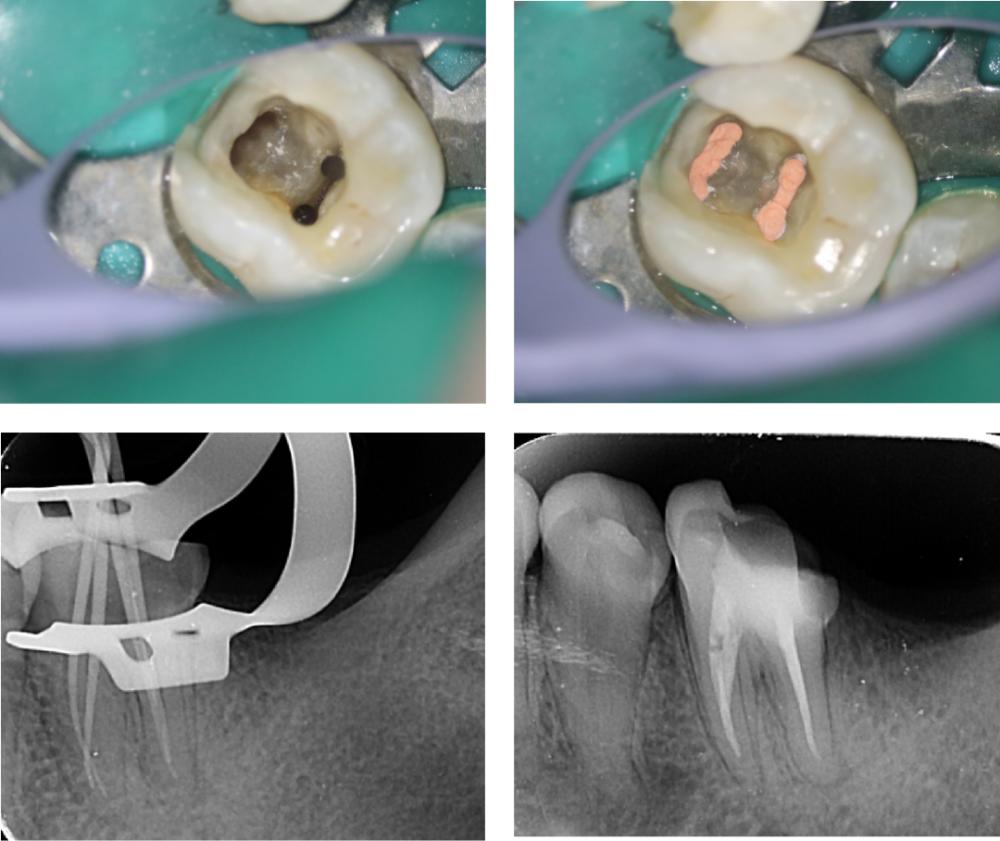

根管治疗有成为牙髓治疗,主要是将根管内的炎症牙髓和坏死物质进行清除,消毒后进行填充治疗。

一般情况下,牙齿龋坏严重、严重的牙齿隐裂引起牙髓坏死,出现炎症以及根尖炎症并且无法进行保髓治疗的情况需要进行根管治疗。